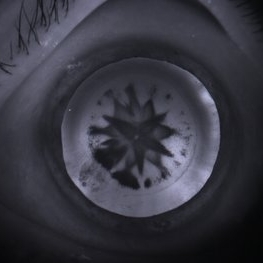

Traumatic Cataract Rossette

Apr 24 2015 by Mehul A Shah

25-year-old male presented with complaint of blunt trauma, presented after 3 week as rosette cataract picture shemoflage retro illumination.

Photographer: Mehul Shah, Drashti Netralaya

Imaging device: Zeiss FF450plus

Condition/keywords: rossette cataract, traumatic cataract